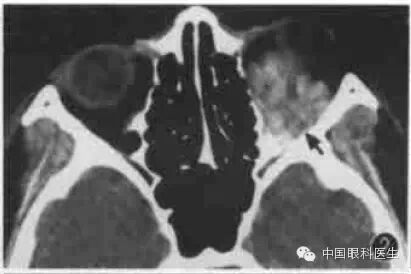

炎性假瘤是常见的眶内占位病变,CT显示病变多位于眶前部,并附于或包裹正常结构如眼球、眼外肌或视神经。病变形状不规则,边界不清楚,多数病变累及双侧眼眶。部分弥漫性炎性假瘤可波及眶内所有结构,呈全眶腔弥漫性密度增高,眶内正常结构均被遮盖(图9)。

图9双侧炎性假瘤,CT显示右眼球高度突出,球后被高密度病变遮盖,正常结构消失。左眶内下方扁平形占位病变,双侧筛窦和蝶窦浑浊,筛窦骨壁轻度增生